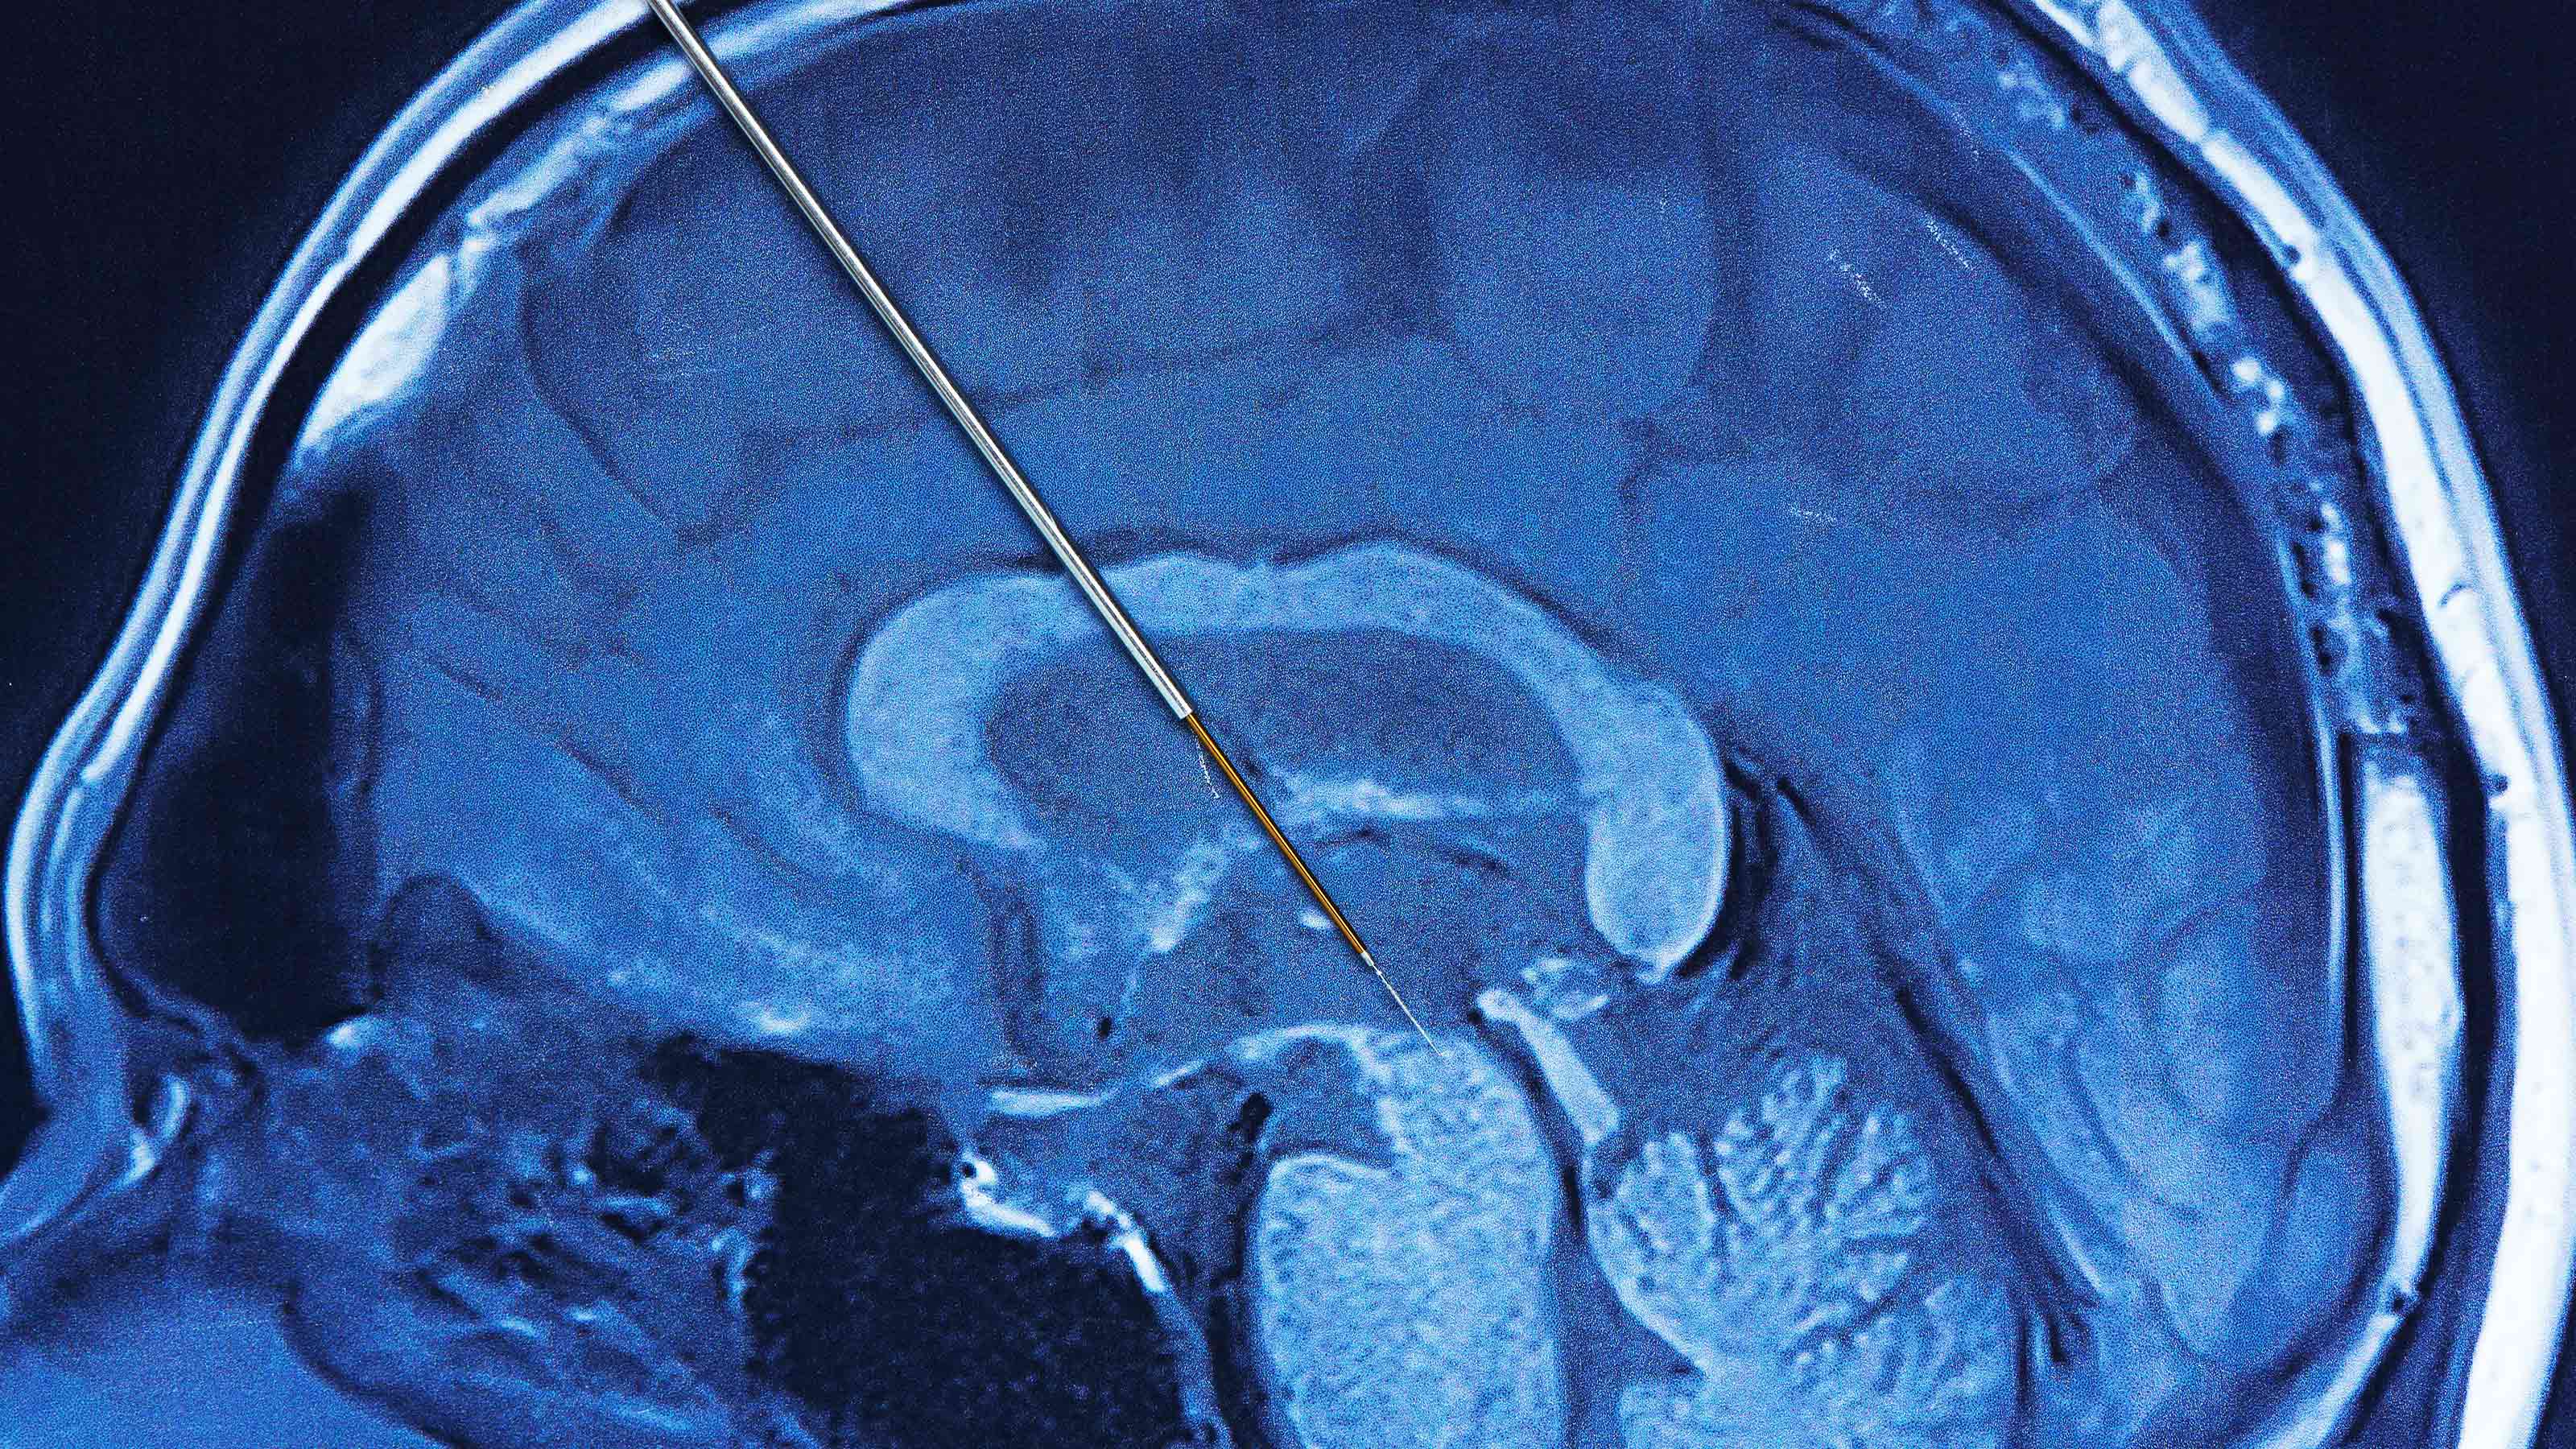

Flexible brain implant tested in people for the first time

Startup Precision Neuroscience has tested its flexible, ultra-thin brain implants in people for the first time.

deep brain stimulation